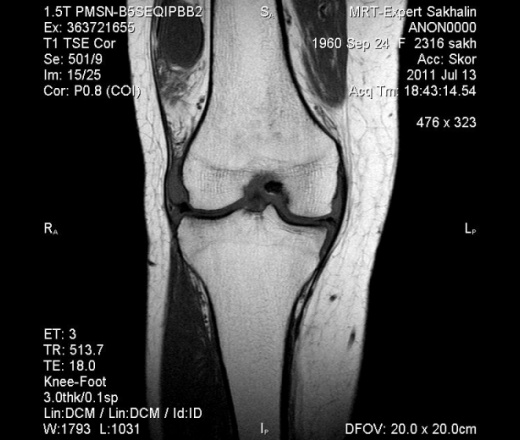

ID:53621

А контраст не вводили? Я бы дифференцировал с виллонодулярным синовитом.

Евгений Петрович, спасибо!Контраст не вводили.

Написала : признаки пролиферативного синовита, хондроматоза.

Неоднозначно всё